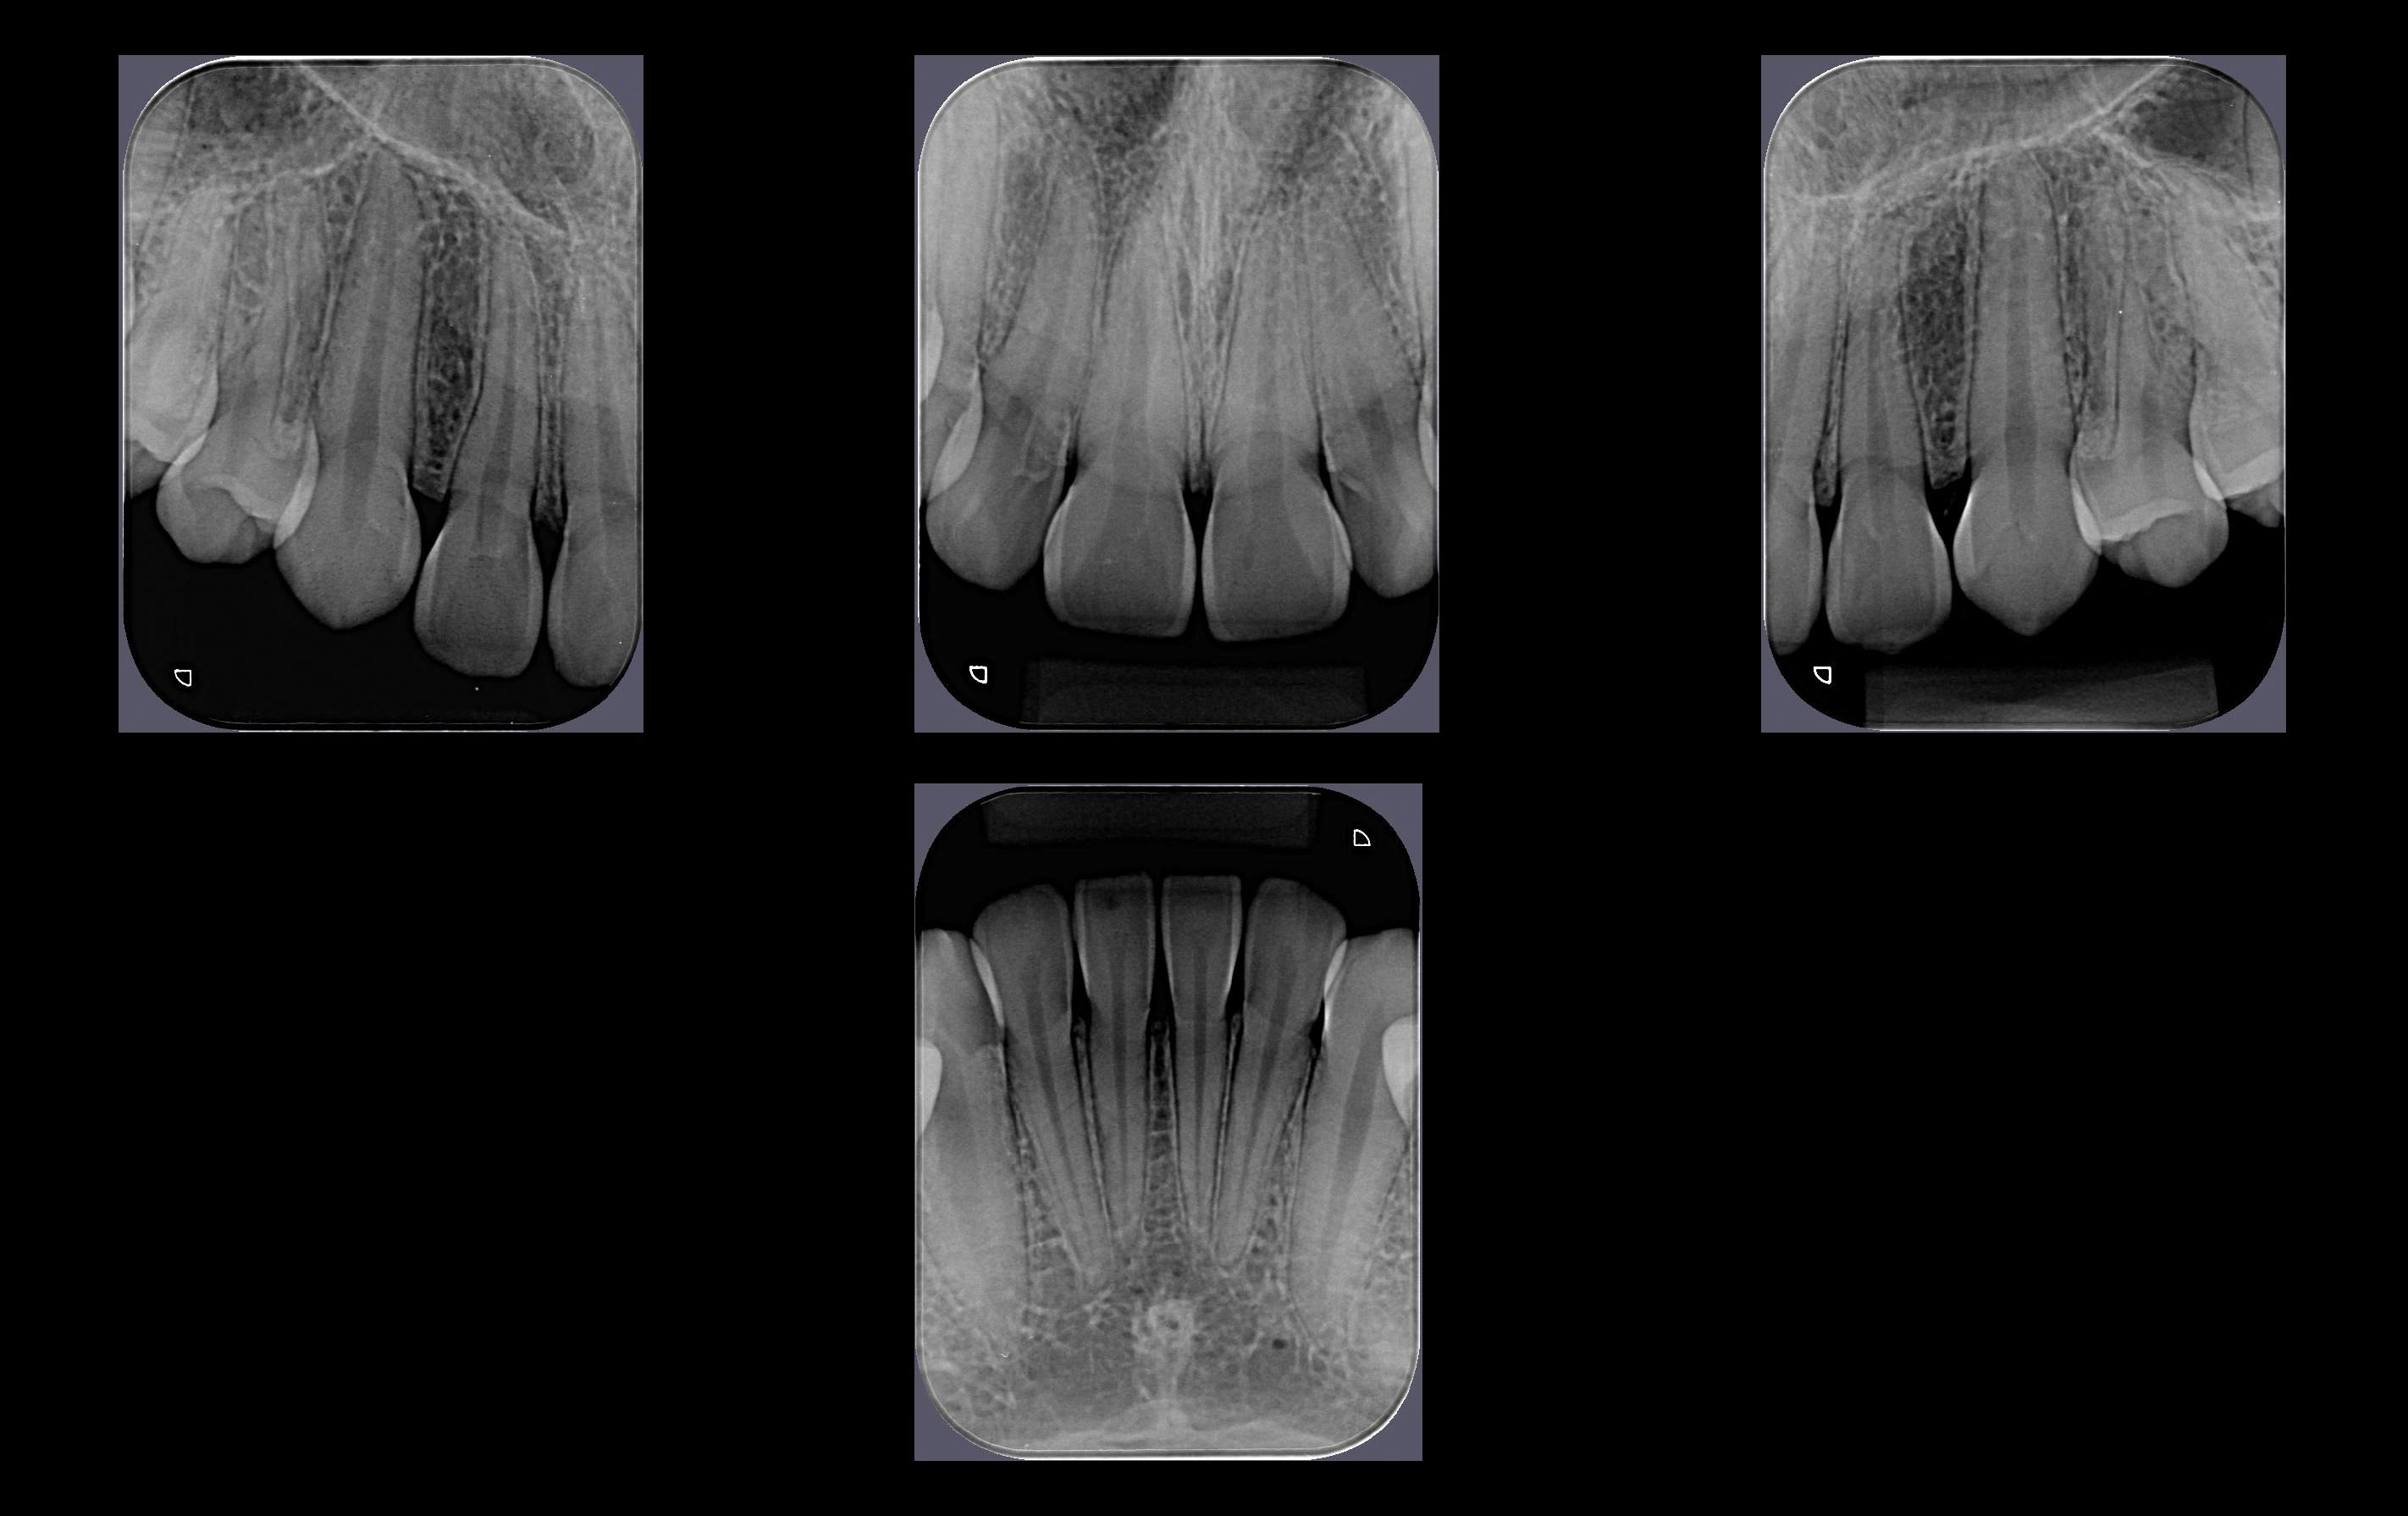

Técnica radiográfica Intrabucal, dividida em regiões especificas com imagem detalhada dos incisivos centrais, incisivos laterais, caninos, pré-molares e molares. Tem por objetivo mostrar detalhadamente os elementos dentais e os tecidos ósseos adjacentes.

• Avaliação periodontal;

• Observação de lesão ou cisto periapical;

• Avaliação pós-traumática dos dentes e do osso alveolar;

• Avaliação da presença e posicionamento de dentes não-erupcionados;

• Avaliação da morfologia radicular antes das extrações;

• Procedimentos endodônticos, para o conhecimento da forma anatômica, número de raízes e condutos radiculares;

• Avaliação de fraturas;